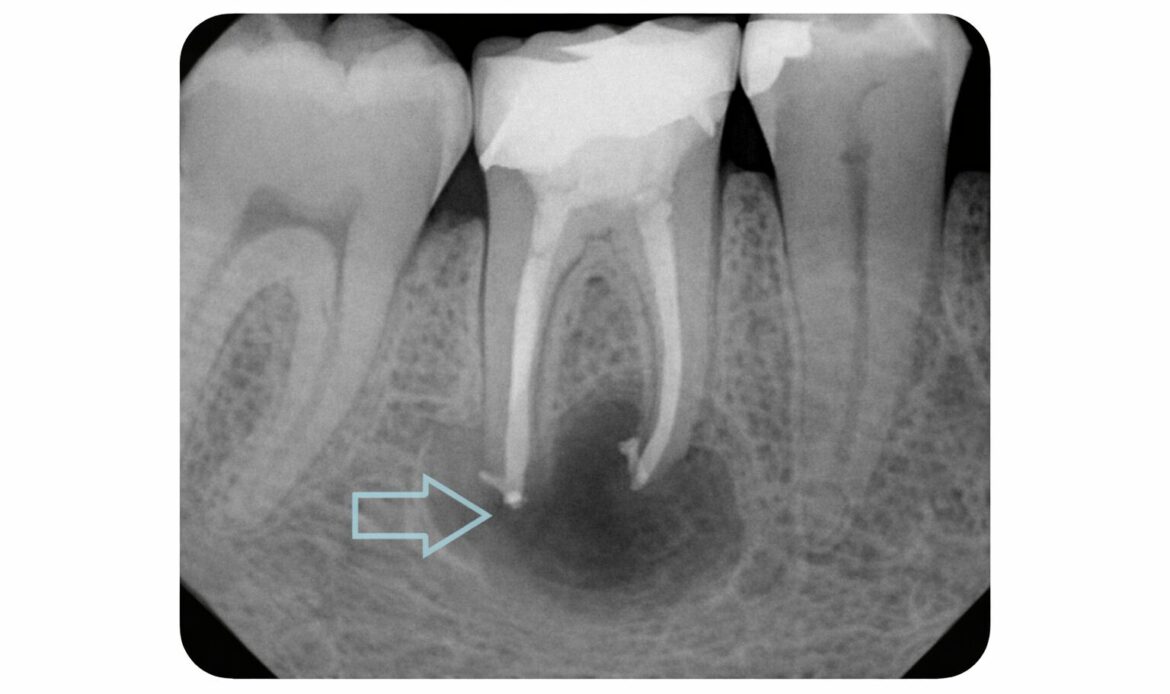

A dental infection can start with one sore tooth or a strip of irritated gums, but the next steps are not the same. Knowing whether the problem is more likely a tooth infection or a gum infection can help Houston, TX patients get the right care faster and avoid a small issue turning into a […]